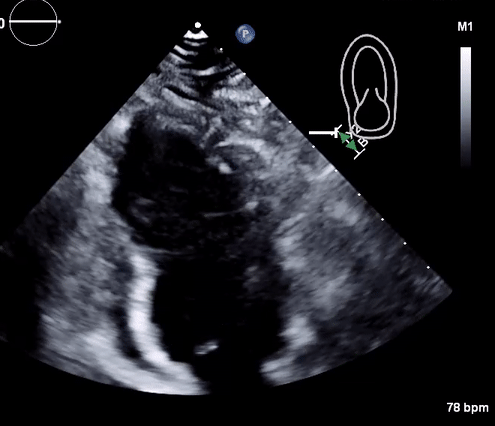

Physical, mental, and emotional stressors have been well known to adversely affect cardiac function. A rare complication of such stressors is stress cardiomyopathy, otherwise known as takotsubo cardiomyopathy. First identified in Japan in the 1990s, takotsubo cardiomyopathy classically presents with systolic dysfunction and apical ballooning. In this report, we present the case of a patient with a medical history of alcohol abuse who presented to the emergency department after being found unresponsive by her family. Transthoracic echocardiography revealed takotsubo cardiomyopathy, which was likely secondary to alcohol withdrawal. Alcohol withdrawal causes an imbalance between various neurotransmitters such as GABA and glutamate. This imbalance caused autonomic overactivity, which manifested as stress cardiomyopathy.